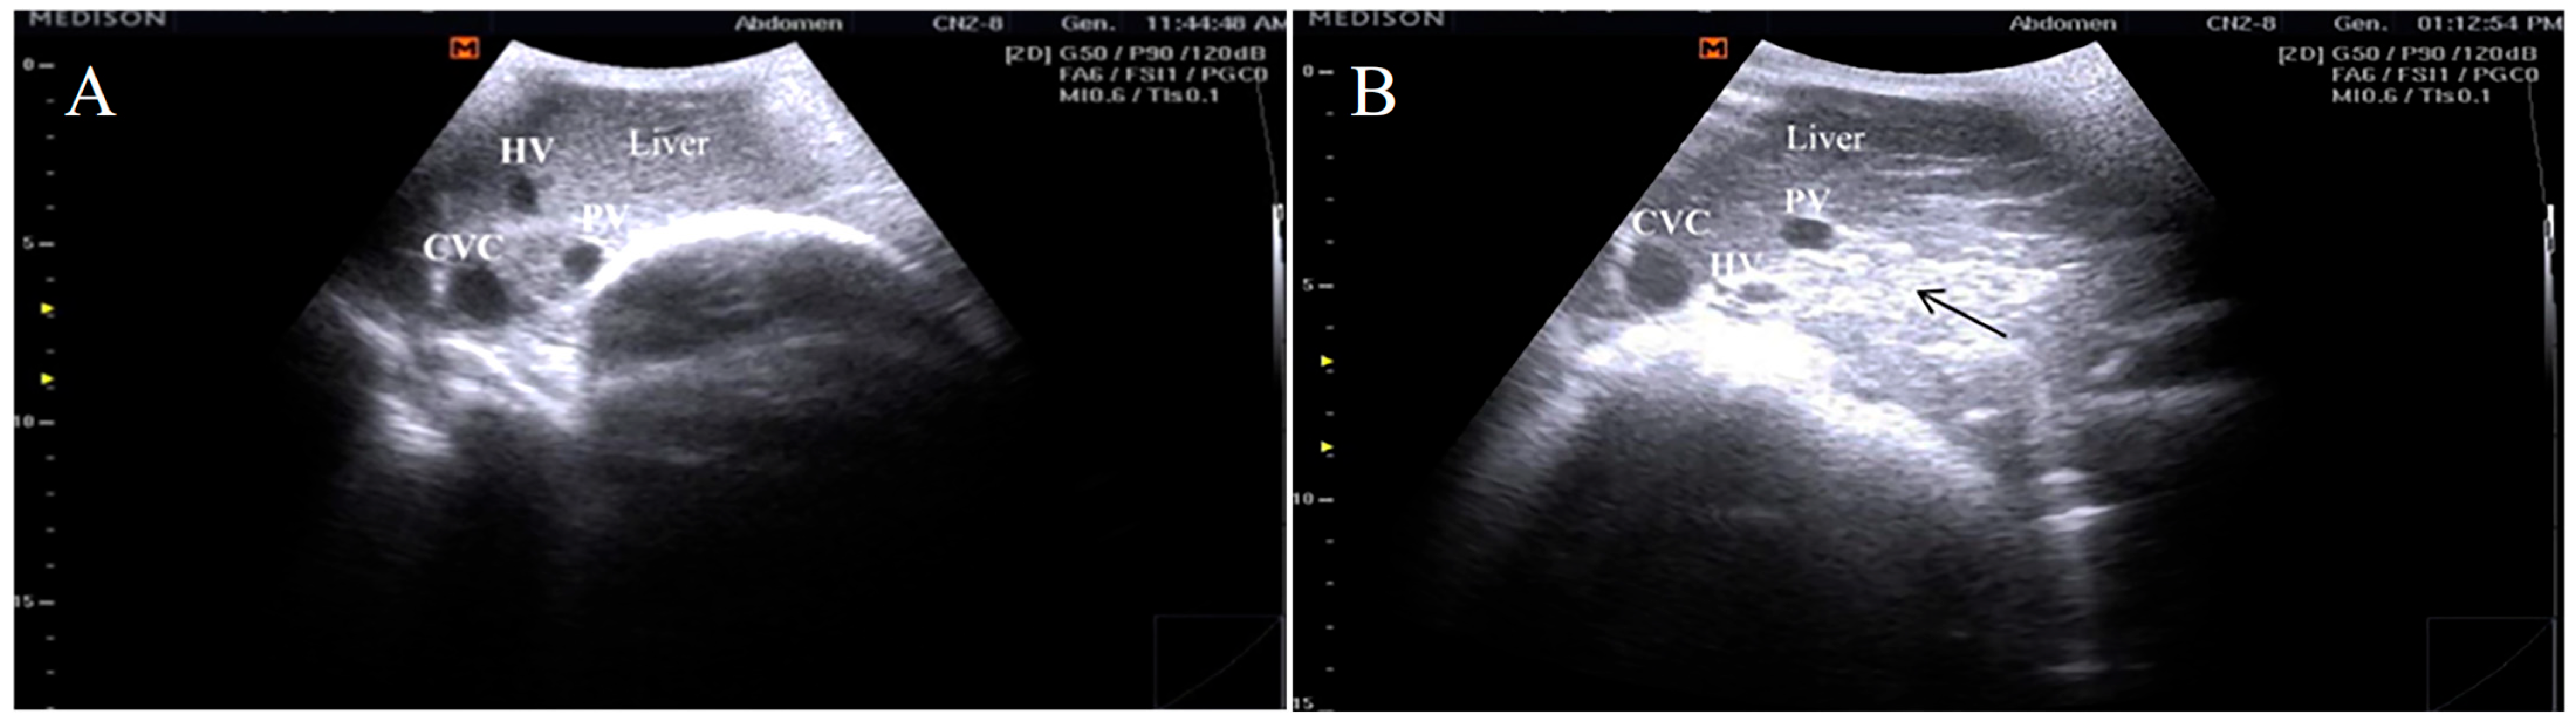

3.2. Ultrasonographic Findings

- Hassan, H.; Kamr, A.; Elkholy, A.; Arbaga, A. Conventional and Doppler ultrasonographic diagnosis of subclinical pregnancy toxemia with altered serum cortisol and biochemical parameters in pregnant does. Res. Vet. Sci. 2024, 176, 105337. [Google Scholar] [CrossRef]

- Tharwat, M.; Alkheraif, A.A.; Marzok, M. Pregnancy toxemia in small ruminants: Clinical, sonographic, hematobiochemical and pathologic findings. Int. J. Vet. Sci. 2024, 14, 204–2011. [Google Scholar]

- Arbaga, A.; Hassan, H.; Elkholy, A.; Kamr, A. Hepatic B-mode Ultrasonography for the Diagnosis of Does Subclinical Pregnancy Toxemia with Special Reference to Hematological Alterations. J. Curr. Vet. Res. 2023, 5, 80–86. [Google Scholar] [CrossRef]